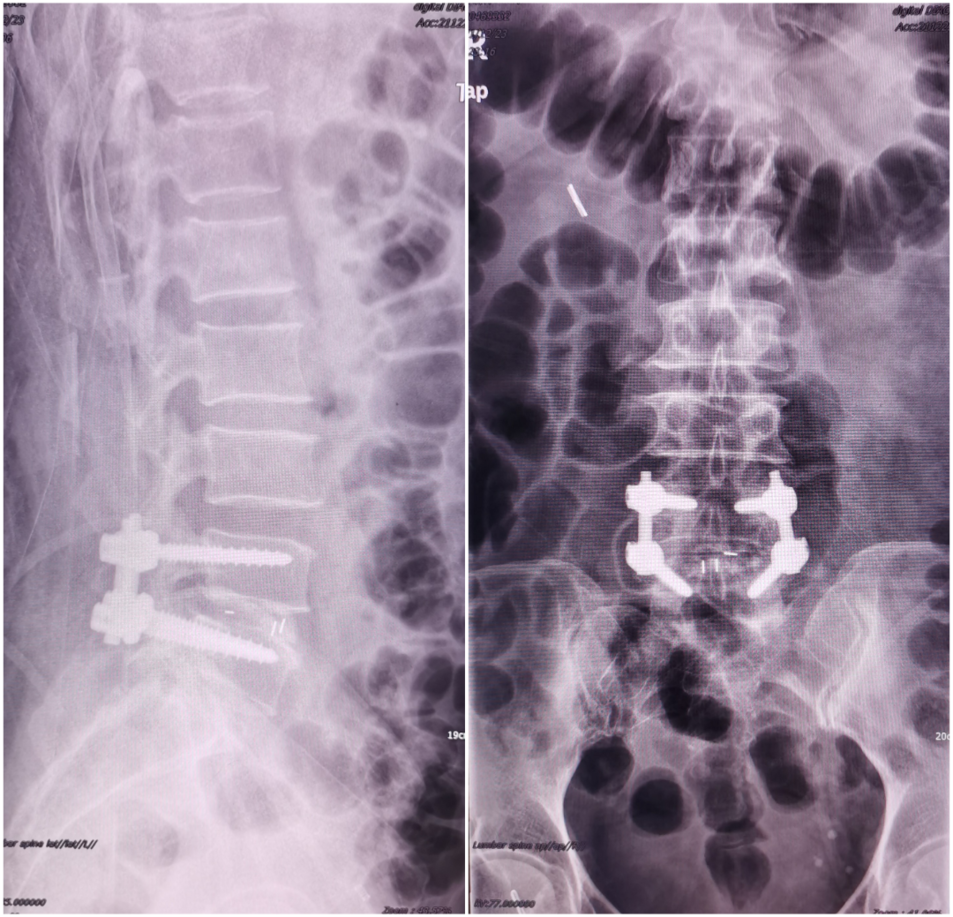

腰椎微创融合(MIS-TLIF)

患者陈某,中年女性,反复腰痛9年余,加重伴左下肢放射痛、麻木1月入院,查体:脊柱生理弯曲存在,腰部未扪及台阶感,腰椎间隙稍压痛,椎旁肌压痛及叩击痛,左下肢稍萎缩,左下肢肌力4级,左大腿、小腿外侧及足背外侧感觉麻木,左侧膝反射及跟腱反射减弱,右下肢肌力感觉正常,双下肢肌力正常,结合辅助检查,诊断:腰4/5椎间盘突出症,于全麻行MIS-TLIF入路腰4/5髓核摘除、椎管扩大减压神经根松解、椎间融合器植骨融合内固定术,术后第二天佩戴护具下床活动,恢复良好。

术前影像学

术后影像学检查